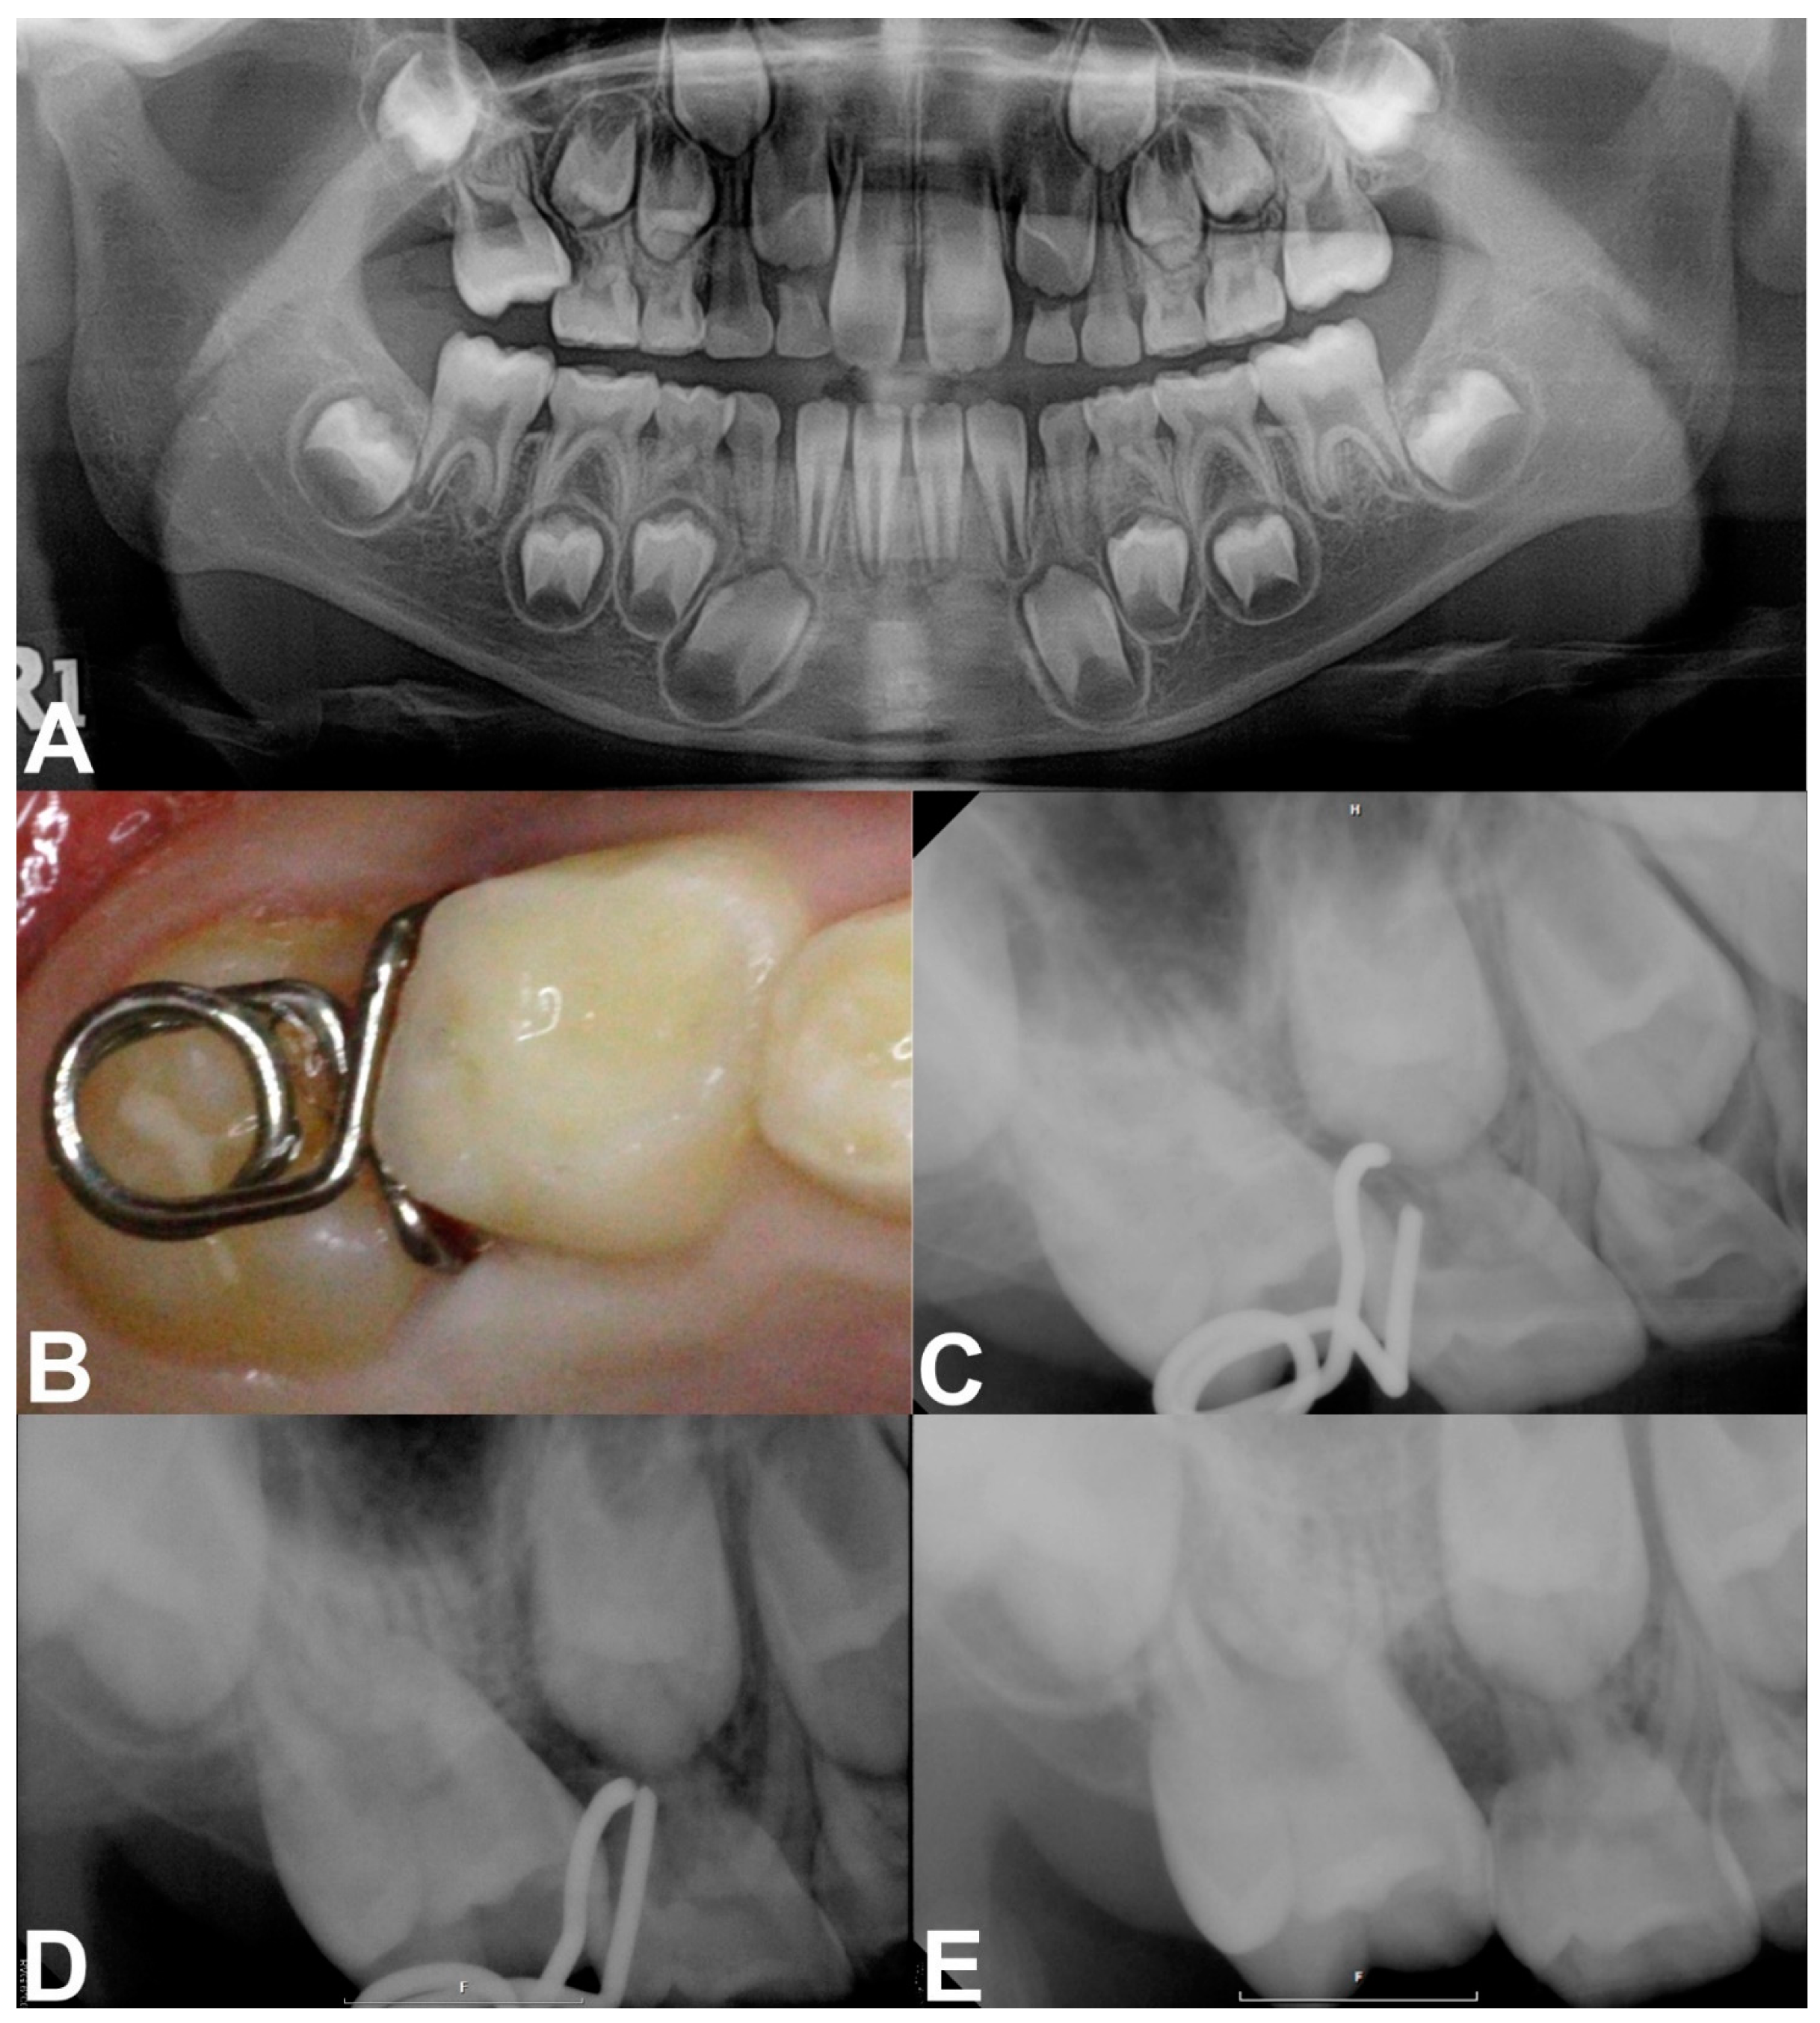

Case 1: A 7-year-old boy without a history of systemic disease presented with a chief complaint of delayed eruption of the left maxillary permanent first molar. A panoramic radiograph showed 2.2 mm deep entrapment of the left maxillary first molar with considerable distal root resorption of the adjacent primary second molar; early loss of the right maxillary primary second molar and, left maxillary and mandibular primary canines, and congenitally missing right mandibular lateral incisor (Figure 2A).

We decided to unlock the left maxillary first molar using a mRS based on these clinical and radiographic evaluations. We planned the space regaining treatment of the right maxillary second premolar and left maxillary canine to take place several years later in the late mixed dentition period. The mRS was inserted after the infiltrative anesthesia (Figure 2B,C). The horizontal spring was placed on the distal cusp of the first molar without any discomfort or mucosal irritation (Figure 2C). One month after delivery, the mesial entrapment of the first molar was relieved (Figure 2D). Three months later, the maxillary left first molar was successfully unlocked and reached the same occlusal level as the adjacent primary second molar (Figure 2E). Resorption of the mesiobuccal root of the left maxillary primary second molar was observed with slightly increased mobility (Figure 2E); however, we maintained the primary second molar until its spontaneous exfoliation. The patient did not report any discomfort during this treatment. The two-year follow-up panoramic radiograph showed undisturbed full eruption of the left maxillary premolars (Figure 2F). As the patient’s left maxillary second premolar and right maxillary canine were fully erupted compared to their counterparts, we plan to initiate space regaining treatment by shifting the molars posteriorly.

Figure 2. Pre-treatment and treatment progress images of case 1. (A) Pre-treatment panoramic radiograph at 7 years of age. (B,C) Clinical photograghs after the insertion of mRS. (D) Periapical radiograph obtained 1 month after delivery, showing relieved locking. (E) Post-treatment radiograph showing the successfully corrected left maxillary first molar with proper occlusion after 3 months. (F) Post-treatment panoramic radiograph taken at 9 years of age. Left maxillary premolars fully erupted without space deficiency.